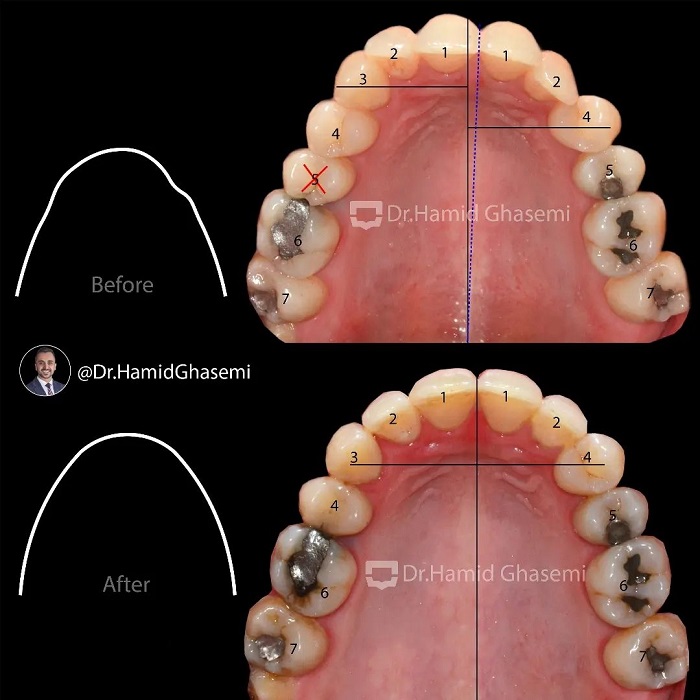

درمان ارتودنسی بدون جراحی در کیس با مشکل انحراف آرچ فکی و لبها ناشی از کشیدن یکطرفه دندان نیش فک بالا 👈👈 در این کیس به علت کمبود فضا و رویش دندان نیش خارج از قوس فکی دندانپزشک بدون مشاوره ارتودنسی اقدام به کشیدن یکطرفه دندان نیش سمت چپ بالا در سنین نوجوانی کردند و در نتیجه انحراف آرچ فکی و به دنبال آن انحراف لبها اتفاق افتاد. درمان در مدت ۲۴ ماه بدون هيچ گونه جراحی فک و جراحی بافت نرم با کشیدن یکطرفه دندان پرمولر دوم در سمت راست جهت چرخش آرچ فکی بالا به سمت راست انجام شد. دندان پرمولر اول سمت چپ جایگزین دندان نیش کشیده شده در سمت چپ شد. به تغییرات قابل توجه در بهبود قرینگی لبخند و لبها توجه کنید که به واسطه اصلاح آرچ فکی حاصل شد.

Non surgical orthodontic treatment of case with upper arch and lips asymmetry due to unilateral extraction of upper canine 👉👉 In this case due to lack of space and displaced upper left canine out of dental arch the dentist attempted to extract upper displaced canine without orthodontic consultation in adolescent and as a result upper arch and lips asymmetry occured. Treatment done for her within 24 months without any surgical procedures on jaws and lips by unilateral extraction of upper right 2nd premolar in order to shift upper arch to the right and then upper left 1st premolar substituted for missing canine on left side. Take note on significant Improvement of lips symmetry followed by correction of upper arch asymmetry